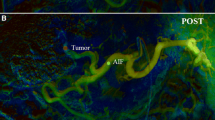

The paired comparison allowed a side-by-side evaluation of DSA and DVA images in a blinded and randomized manner. DVA was the preferred image in 80% of comparisons (Fig. 4, left panel), and the average score (mean ± SEM) of the whole image set was 1.44 ± 0.21, the median score was 1.60 (IQR 2.4), significantly different from 0 (one-sample Wilcoxon p < 0.001), which represented the equal quality level, indicating the superiority of DVA images (Fig. 4, right panel). The interrater agreement was also significant (Kendall’s W value: 0.575, p < 0.001). Representative image pairs are shown on Fig. 5.

Comparison of a representative DSA (left panels) and DVA (right panels) image pairs. More millimetre to submillimetre arterial vessels can be depicted on the DVA images, and both the lesions and the feeding arteries can be evaluated more clearly. The DSA and DVA images were generated from the same unsubtracted image series using the Siemens Syngo or the Kinepict Medical Imaging Tool software, respectively